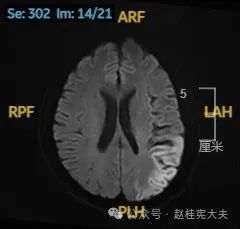

头颅磁共振平扫提示左侧颞枕叶亚急性期脑梗死可能。头颈部CTA示左侧椎动脉颅内段发育不良。头颅磁共振增强+波谱分析提示左侧颞枕叶病灶,考虑脑炎可能大。

入院后给予精氨酸,左卡尼丁,辅酶Q10,维生素E等治疗。患者病情稳定好转中,2天后意识清楚,语言表达仍欠佳。当天复查颅脑磁共振如下:

以上为患者发病后3次的颅脑磁共振片子,临床诊断基本上可以确认了,希望患者逐渐恢复!